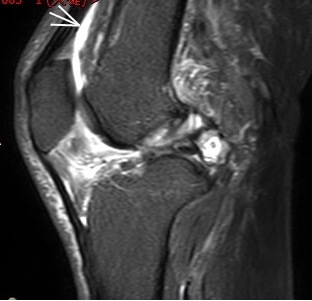

2. 運動后“打軟腿”——韌帶的“斷弦危機”

場景:打球急停后膝蓋不穩(wěn),走路像“踩棉花”

MRI偵查:揪出前交叉韌帶斷裂(呈“波浪狀”或連續(xù)性中斷)、內(nèi)側(cè)副韌帶損傷,防止關(guān)節(jié)“脫軌”

(內(nèi)側(cè)副韌帶損傷)